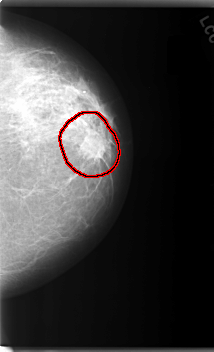

C_0116_1.LEFT_CC

LEFT_CC LINES 5968 PIXELS_PER_LINE 3632 BITS_PER_PIXEL 12 RESOLUTION 50 OVERLAY

FILE: C_0116_1.LEFT_CC.OVERLAY

TOTAL_ABNORMALITIES 1

ABNORMALITY 1

LESION_TYPE MASS SHAPE IRREGULAR MARGINS SPICULATED

ASSESSMENT 5

SUBTLETY 5

PATHOLOGY MALIGNANT

TOTAL_OUTLINES 1

BOUNDARY